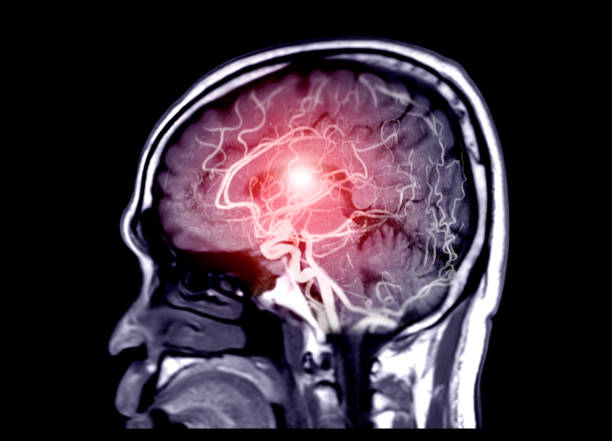

뇌출혈은 뇌안에 있는 혈관에서 출혈이 발생하여 뇌조직이 손상을 입는 질환이며, 중증의 뇌혈관질환 중 하나입니다. 일반적으로 고혈압, 동맥류, 혈관 기형, 혈전 등의 이유로 혈관이 파열하거나 뚫리면서 발생합니다.

뇌출혈은 갑작스러운 발작, 의식 잃음, 경련, 혼란, 언어 장애, 편마비 등의 증상을 일으키며, 이러한 증상이 발생하면 즉시 의료진의 진료를 받아야 합니다. 뇌출혈은 치료가 지연되면 심각한 후유증을 일으킬 수 있으므로, 조기 발견과 적절한 치료가 필요하기 때문에 이번 시간에는 뇌출혈 전조 증상에 대해 자세히 알아보겠습니다.